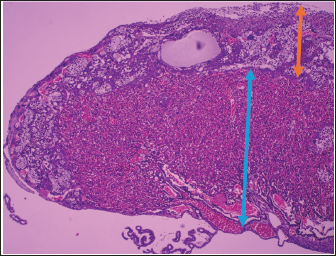

Microscopic analysis supported these findings, with Figures 1 and 2 demonstrating clear histological differences. Inflammation characterized by erythrocyte infiltration (blue arrows) was more apparent in the labyrinth layer of the EG, whereas necrotic cell presence (green arrows) was identified in the decidua basalis layer, suggesting that placental integrity may be disrupted by EMW exposure during gestation. Additionally, the tissue structure in the EG appeared more irregular and degenerated than the well-organized CG cellular architecture.

Fig. 2. Histological section of the placenta of a pregnant mouse at gestational age. (H&E staining, 100 ×, scale bar ≈ 100 µm). The orange arrow indicates the decidua basalis, which is the maternal component of the placenta and consists of large decidual cells with eosinophilic cytoplasm and supporting connective tissue. The blue arrow indicates the labyrinth zone, the fetal component of the placenta characterized by abundant vascular spaces and thin trophoblastic septa, which is the main site of maternal–fetal exchange.